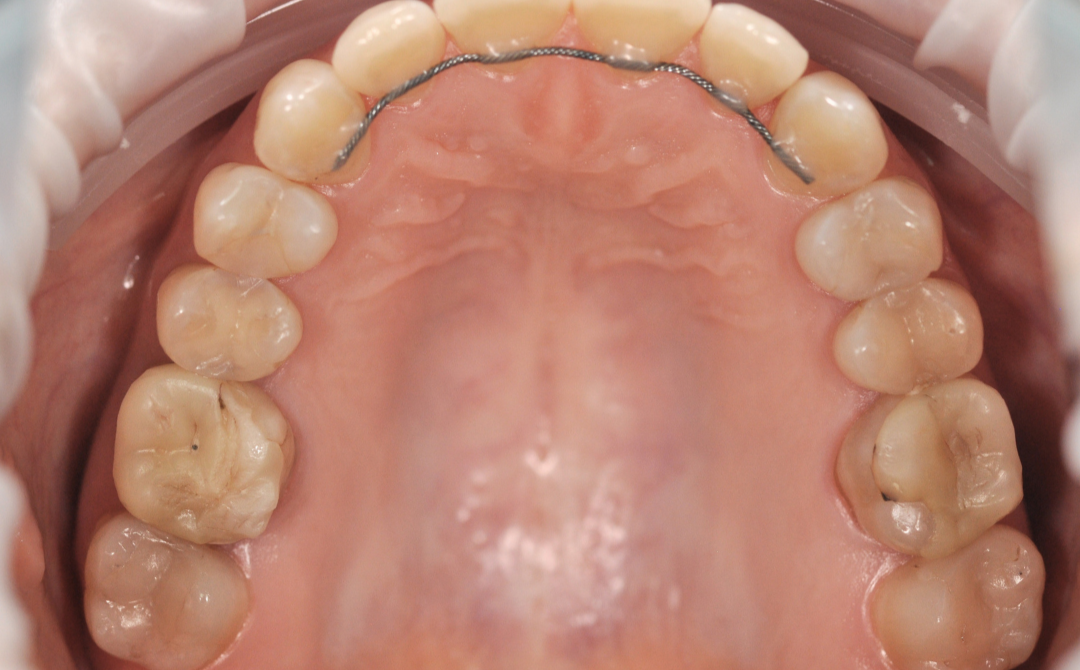

Этап №4

Финишная реставрация.

После снятия брекет-системы стоматолог-терапевт провела художественную реставрацию формы боковых резцов, добившись идеальной гармонии и естественности улыбки.

Результаты комплексного лечения

Комплексный подход команды «Архитектор Улыбок» дал закономерный результат, который был спрогнозирован еще

до старта лечения.

Здоровая улыбка

Ушел дискомфорт в суставе, исчезли боли в процессе жевания. Нижняя челюсть заняла стабильное, физиологичное положение.

Восстановилась функция

Качество жевания кардинально повысилось, процесс приема пищи снова стал комфортным.

Эстетика

Исправлен прямой прикус, восстановлена форма резцов, а улыбка стала не только красивой, но и здоровой с точки зрения биомеханики.